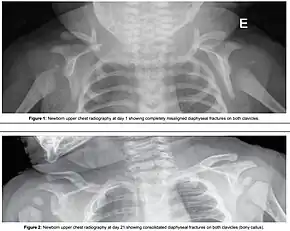

- Intentional causing clavicular fractures, which reduces the diameter of the shoulders that requires to pass through the birth canal;[2]